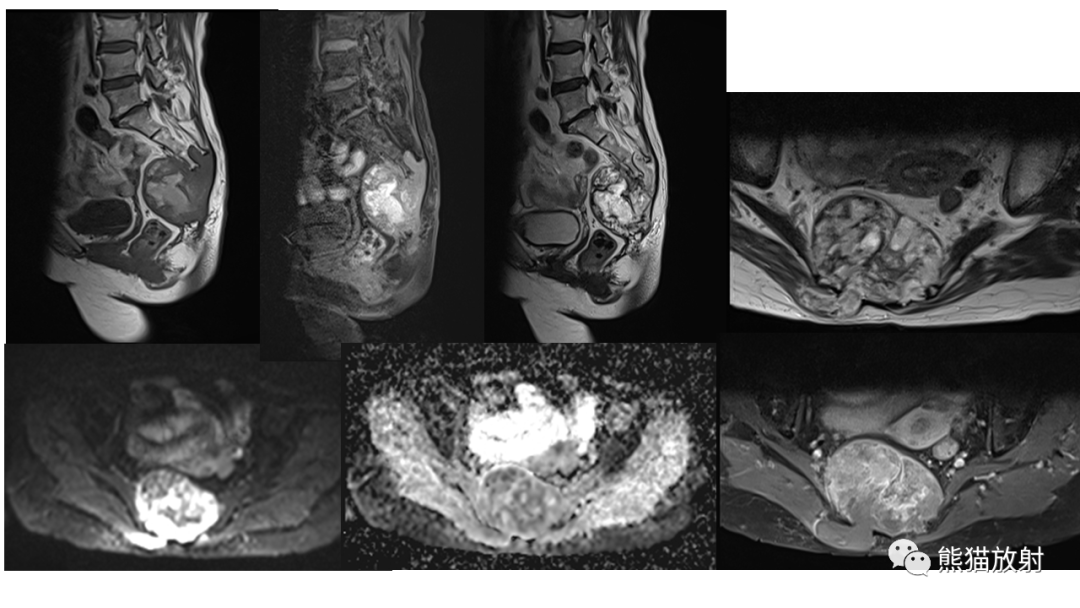

【病例】斜坡 & 骶骨脊索瘤各1例CT及MR-3

【病例】斜坡 & 骶骨脊索瘤各1例CT及MR-4